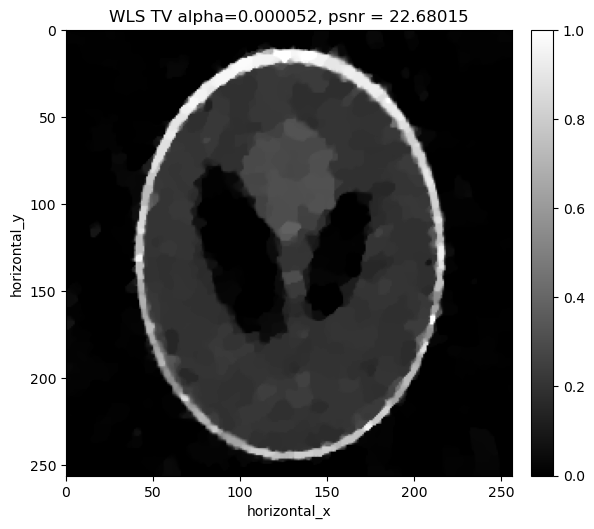

Reconstructing the noisy data using least squares with Total Variation regualrisation#

Similar to the least squares cas, in addition to the weighted least square term, we considered a Total Variation Regulariser. We minimize:

\[||Y-Ax||_{W}^{2} + \alpha \, TV(x)\]

where \(\alpha\) is the regularization parameter that balances the two terms. Again we search a range of values of \(\alpha\) to find the best one for the data.

[27]:

# Selection of the best regularization parameter using WLS TV - FISTA

show2D([recon_wls_tv], ["WLS TV alpha=%7.6f, psnr = %7.5f" % (alpha,psnr_wls_tv_alpha[i])], \

print("alpha=%7.6f, psnr= %5.3f" % (alpha,psnr_wls_tv_alpha[i]))

../../_images/demos_LS_WLS_KL_TotalVariation_40_0.png

../../_images/demos_LS_WLS_KL_TotalVariation_40_1.png

alpha=0.000020, psnr= 18.611

alpha=0.000022, psnr= 19.630

alpha=0.000024, psnr= 20.455

alpha=0.000026, psnr= 21.108

alpha=0.000028, psnr= 21.611

../../_images/demos_LS_WLS_KL_TotalVariation_40_3.png

../../_images/demos_LS_WLS_KL_TotalVariation_40_4.png

alpha=0.000031, psnr= 21.991

alpha=0.000033, psnr= 22.275

alpha=0.000035, psnr= 22.479

alpha=0.000037, psnr= 22.621

alpha=0.000039, psnr= 22.711

../../_images/demos_LS_WLS_KL_TotalVariation_40_6.png

../../_images/demos_LS_WLS_KL_TotalVariation_40_7.png

alpha=0.000041, psnr= 22.762

alpha=0.000043, psnr= 22.781

alpha=0.000045, psnr= 22.778

alpha=0.000047, psnr= 22.758

alpha=0.000049, psnr= 22.725

../../_images/demos_LS_WLS_KL_TotalVariation_40_9.png

../../_images/demos_LS_WLS_KL_TotalVariation_40_10.png

alpha=0.000052, psnr= 22.680